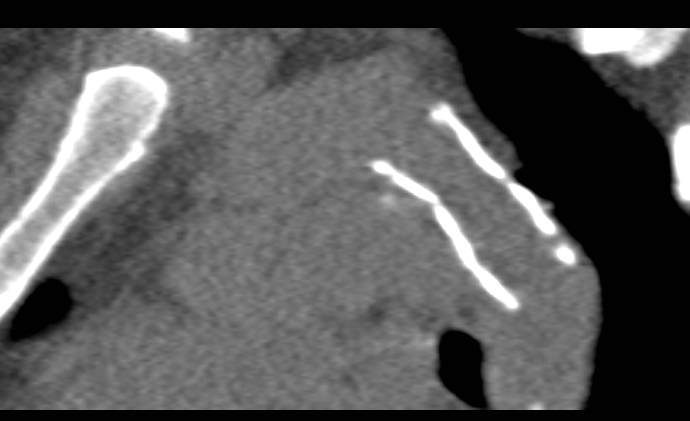

Endovascular Stent Placement in the Thoracic Aorta